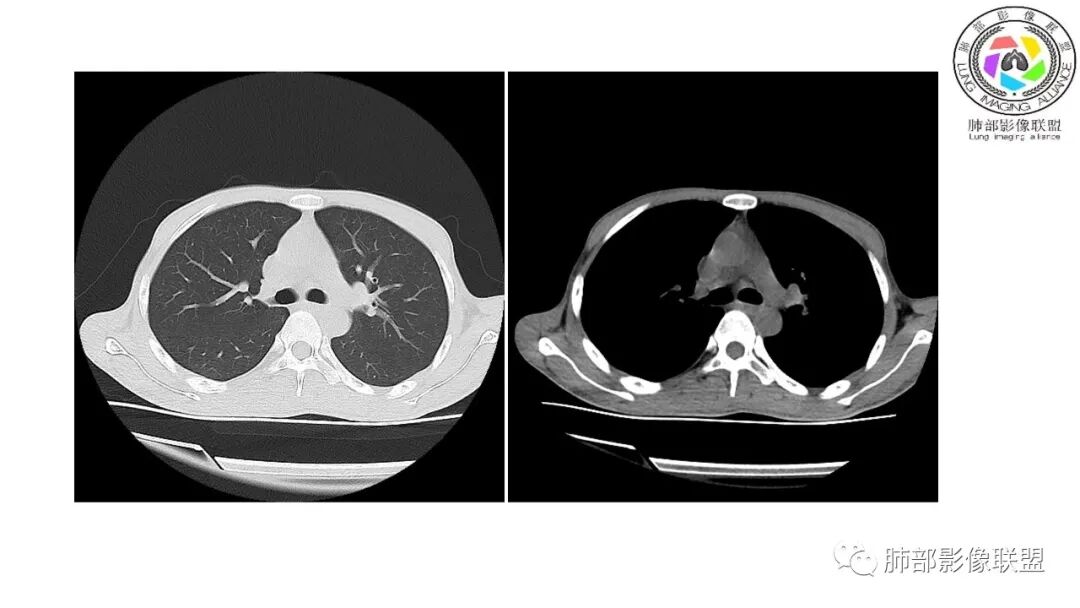

影像与临床:1.青年男性,HlV阳性,颜面部皮疹(未提供皮疹图像)、发热(高热),实验室CRP、PCT高,T-Spot阴性。2.右肺下叶空洞结节,壁厚不均,边界清楚,其内线状影,未见液平及钙化,未见卫星灶,纵隔淋巴结增大,双侧腋窝见增大淋巴结。心腔内低密度提示贫血可能。肝脾影增大,未见结节影及块影。腹膜后见多发增大淋巴结。

综合分析:本例肺部影像学改变并不具有特征性,空洞性病灶须与多种疾病鉴别,但年轻HIV阳性患者,高热,皮疹,肝脾增大,纵隔、腋窝、腹膜后见多发增大淋巴结等都强烈提示马尔尼菲篮状菌感染的可能性。